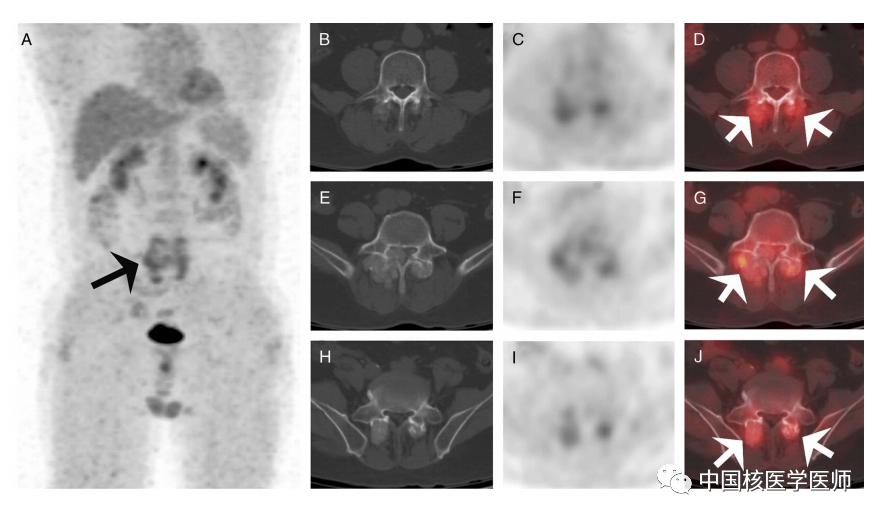

圖2. 為進一步評估病變的代謝活性及可能存在原發性惡性腫瘤,我們對患者進行了18F-FDG PET/CT檢查。MIP PET (圖A,箭頭),同機CT、PET及融合圖像顯示巨大腫塊輕度FDG攝取(SUVmax, 4.2),累及雙側第3(圖B-D,箭頭)、第4(圖E-G,箭頭)椎關節突及第5腰椎(圖H-J,箭頭),依據其臨床病史及血清學結果,提示其可能的診斷為痛風結節。然后,對患者病變處進行活檢,病理結果顯示豐富雙水焦磷酸鈣結晶沉積,而無尿酸鹽結晶,提示疾病為雙水焦磷酸鈣結晶沉積,即沙石假性痛風、突發性沙石痛風。